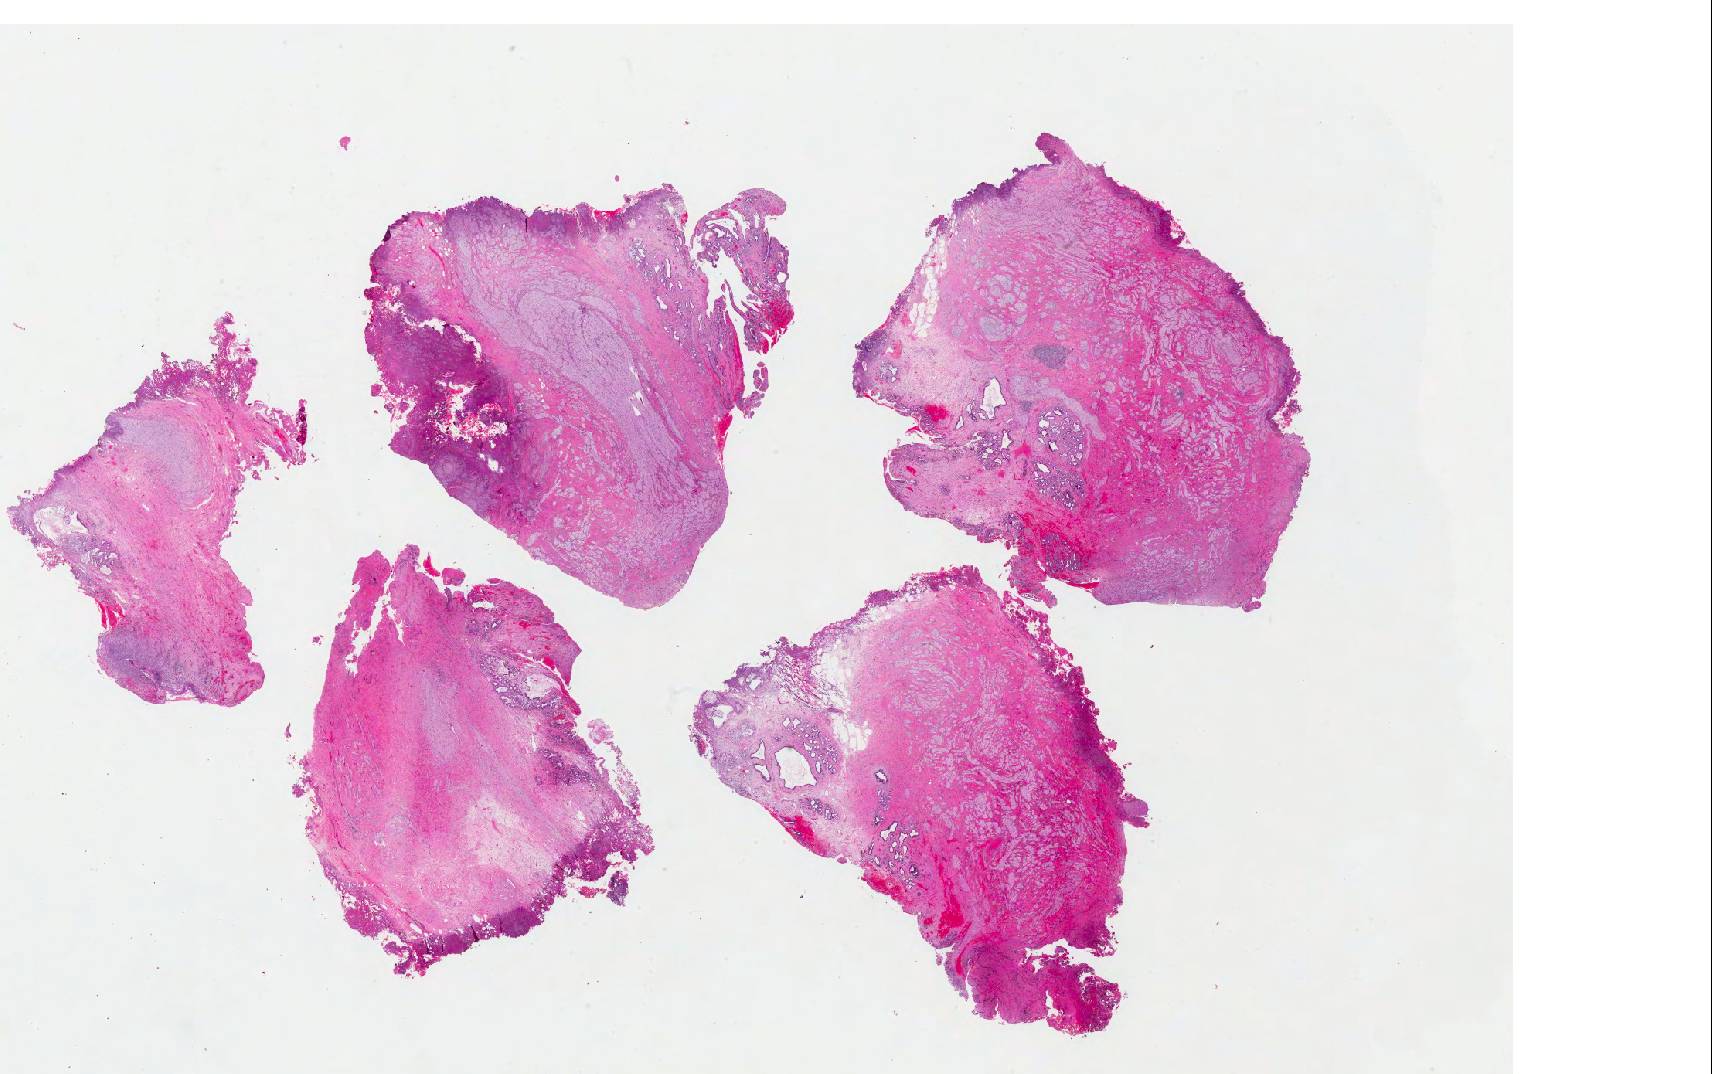

Microscopic images:

Both cases showed disorganized and thickened nerve bundles composed of spindle shaped cells, without atypia. Case A also showed a focal foreign body type giant cell reaction adjacent to the disorganized nerve bundles and a strongly immunoreactive S100 stain.

Histology typically shows hyperplastic nerve bundles, positive for S100.

Microscopic images:

Both cases showed disorganized and thickened nerve bundles composed of spindle shaped cells, without atypia. Case A also showed a focal foreign body type giant cell reaction adjacent to the disorganized nerve bundles and a strongly immunoreactive S100 stain.

Histology typically shows hyperplastic nerve bundles, positive for S100.